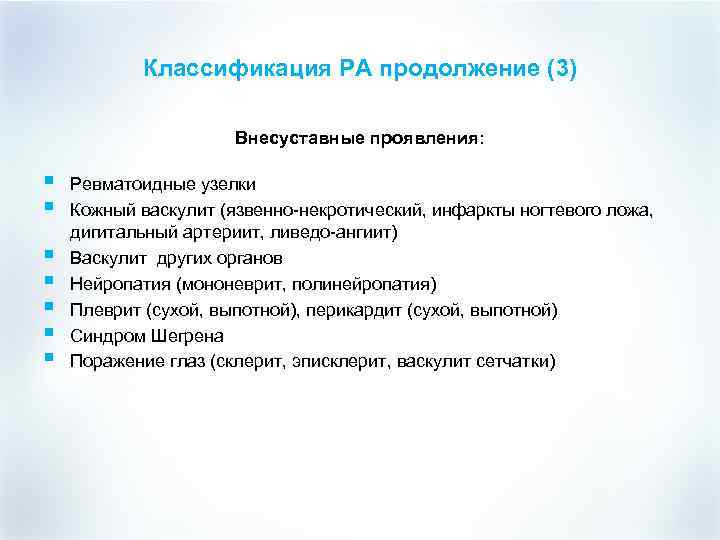

Классификация РА продолжение (3) Внесуставные проявления: § § § § Ревматоидные узелки Кожный васкулит (язвенно-некротический, инфаркты ногтевого ложа, дигитальный артериит, ливедо-ангиит) Васкулит других органов Нейропатия (мононеврит, полинейропатия) Плеврит (сухой, выпотной), перикардит (сухой, выпотной) Синдром Шегрена Поражение глаз (склерит, эписклерит, васкулит сетчатки)

Классификация РА продолжение (3) Внесуставные проявления: § § § § Ревматоидные узелки Кожный васкулит (язвенно-некротический, инфаркты ногтевого ложа, дигитальный артериит, ливедо-ангиит) Васкулит других органов Нейропатия (мононеврит, полинейропатия) Плеврит (сухой, выпотной), перикардит (сухой, выпотной) Синдром Шегрена Поражение глаз (склерит, эписклерит, васкулит сетчатки)